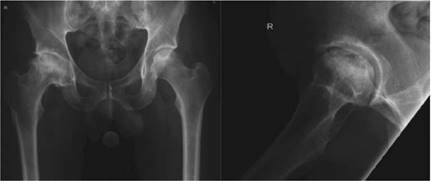

Reproduced from C. Bulstrode et al., Oxford Textbook of Trauma and Orthopaedics second edition, 2011, fi gure 7.16.1, p. 619, with permission from Oxford University Press.

What condition is illustrated here?

Avascular necrosis of the femoral head with segmental collapse.

Can you describe any classifi cation systems for this condition? What stage is shown in the radiographs above?

There are many classifi cation systems described for osteonecrosis of the hip. The Ficat and Arlet (1980) system describes X-ray appearances and is one of the most simple to use:

Stage 1: no bony changes seen on plain X-ray

Stage 2: sclerotic and cystic changes within the femoral head

Stage 3: subchondral collapse and distortion of the femoral head

Stage 4: secondary osteoarthritis with decreased joint space and articular collapse

T he radiographs show Ficat and Arlet stage 4 changes. There is distortion and collapse of the femoral head. The lateral view illustrates the โcrescent signโ associated with subchondral collapse.